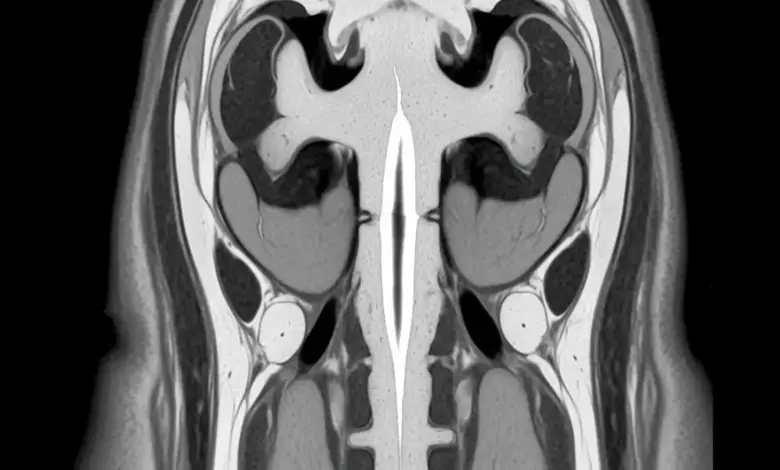

O exame de escolha para investigar siringomielia é a ressonância magnética da coluna, que permite visualizar a medula em detalhes. Com ela, o especialista consegue:

- Identificar a presença da siringe e suas dimensões.

- Localizar exatamente em quais segmentos da medula está a cavidade.

- Verificar se existe malformação de Chiari, tumores ou outras alterações associadas.

- Acompanhar como o quadro muda ao longo do tempo, com retorno periódico e comparação de exames.